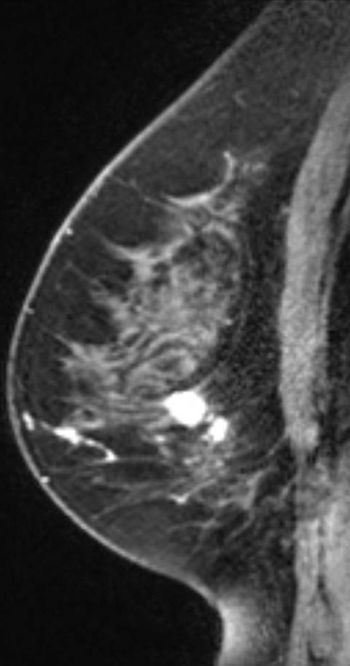

53-year-old BRCA2 positive patient presented for bilateral screening breast MRI.